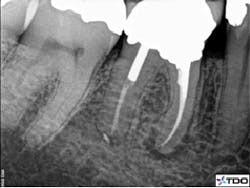

Figure 7 demonstrates a common pitfall of surgery. In this animation the source of bacteria persists in spite of an apical seal. Figures 8 and 9 show the pre- and postoperative views of successful endodontic surgery. Note the choice to approach this case surgically due to the extensive restoration and adequate root canal therapy present in the preoperative image.